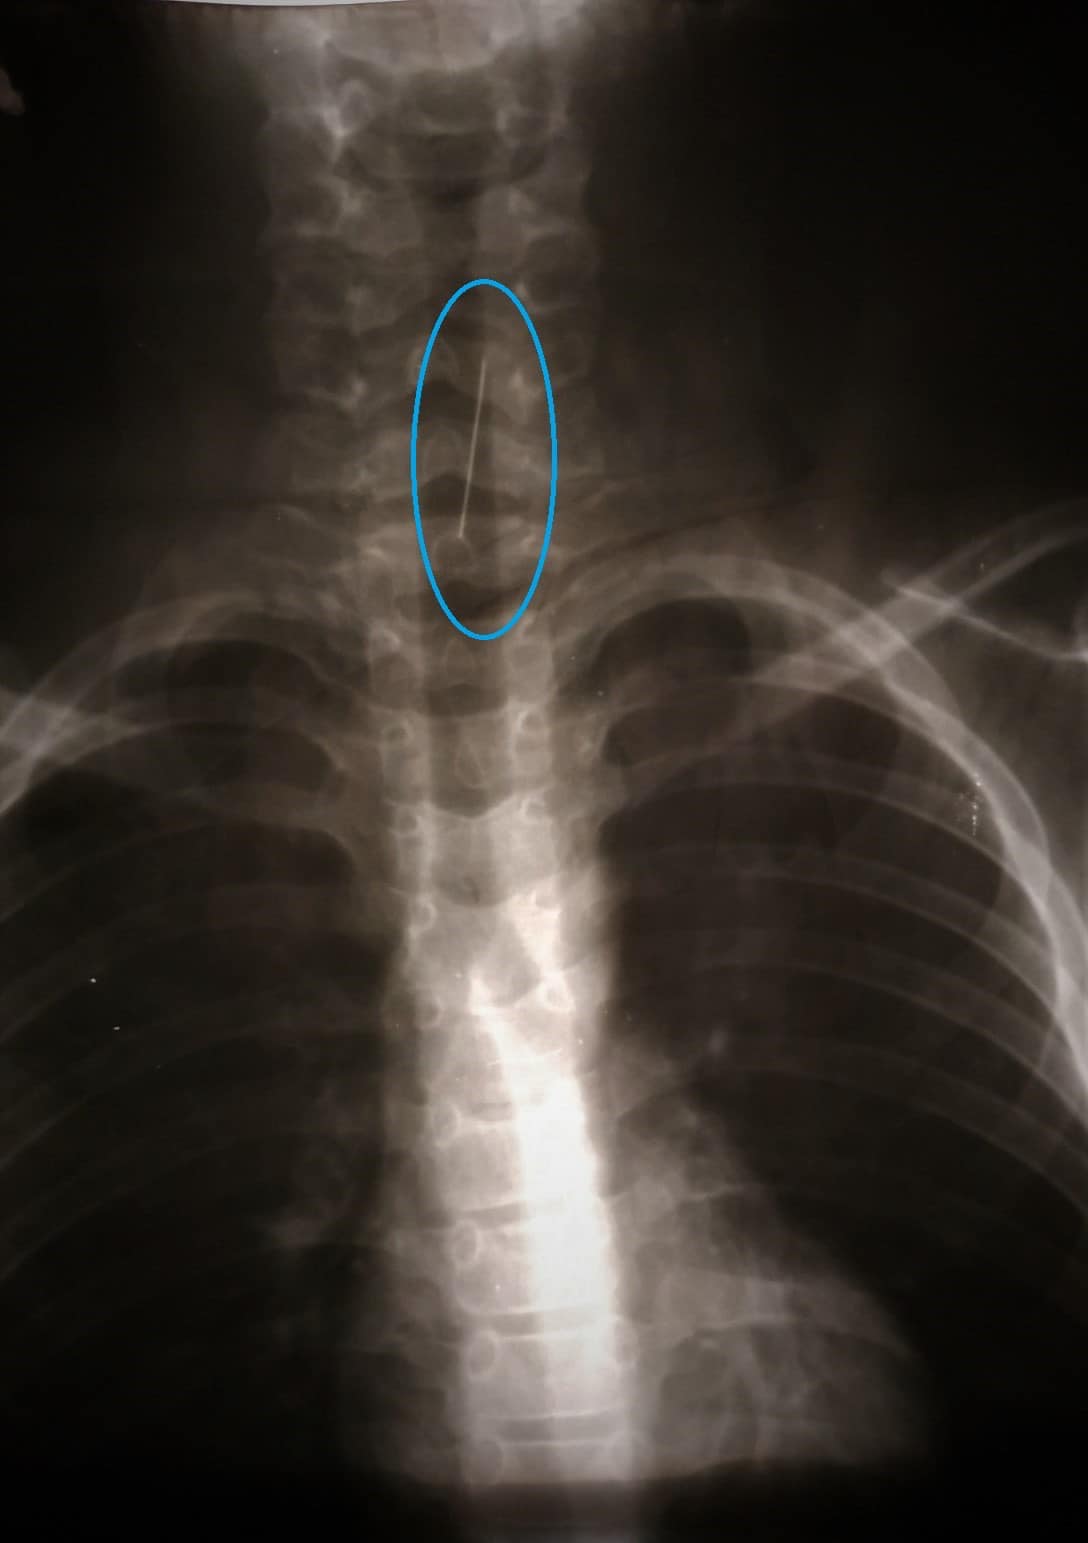

У Дніпрі в лікарню потрапила дитина із булавкою в дихальних шляхах. Зокрема, шпилька встигла підколотися до трахеї, що ускладнило її вилучення.

Так, дитина проковтнула шпильку, і під час діагностичного ендоскопічного дослідження виявилося, що вона підкололася до трахеї.

За словами медиків, вони прорахували різні варіанти розвитку подій та ухвалили вкрай нестандартне рішення, а саме ввести через жорсткий бронхоскоп гнучкий бронхоскоп.

Тому після певних обережних та повільних маніпуляцій їм вдалося видалити злощасну шпильку з дихальних шляхів маленького пацієнта та майже не травмуючи слизову ані бронха, ані трахеї.